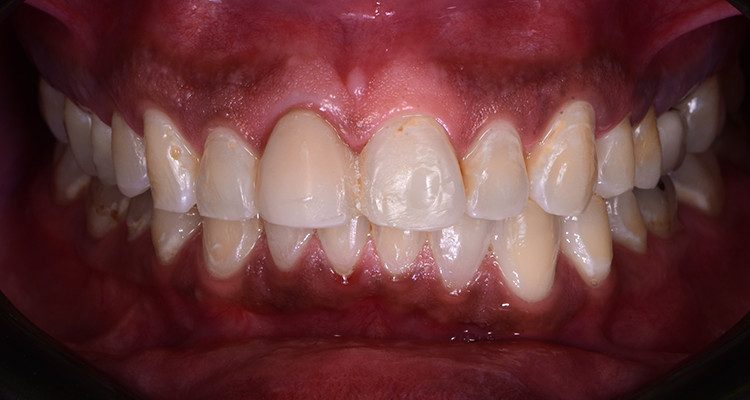

QUEIXA PRINCIPAL: Insatisfação estética do sorriso com envolvimento de forma e cor nos dentes 11 e 21.

Ao procurar atendimento clínico, foi verificada restauração extensa no dente 11 devido a alteração de cor da resina composta associado à restauração insatisfatória.

1 | Imagem intraoral do sorriso em oclusão